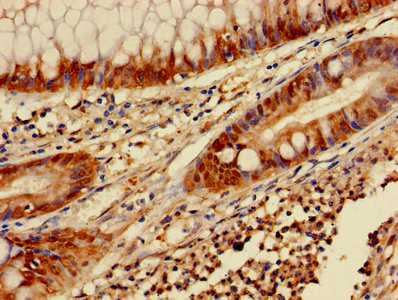

ApplicationELISA, WB, IHC; Recommended dilution: WB:1:1000-1:5000, IHC:1:20-1:200